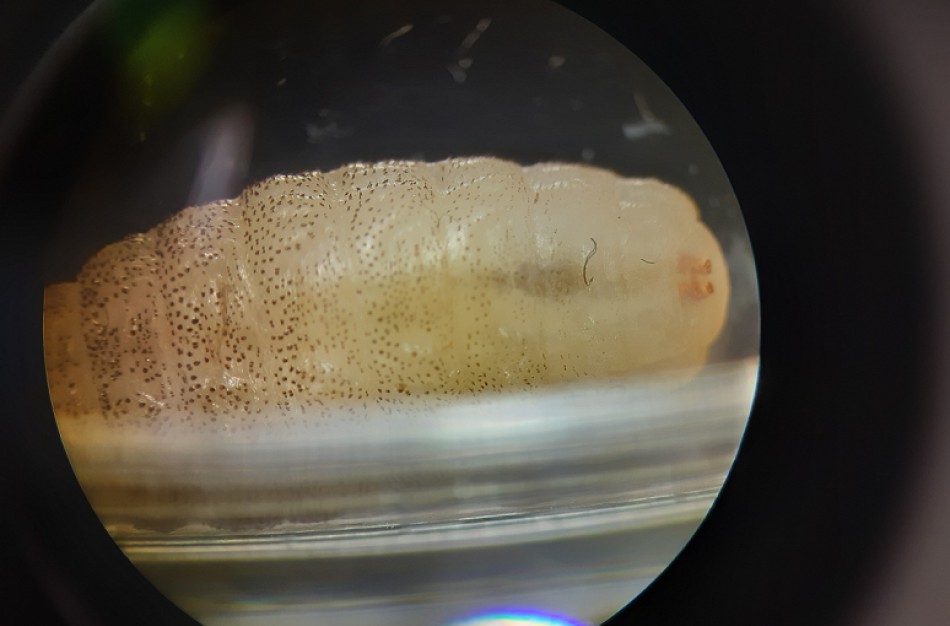

1 paveikslas Taip atrodo Cordylobia anthropophaga musės lerva pro stereoskopinį mikroskopą. Realiai jos ilgis buvo 11 mm, balkšvai gelsva, su juodais dygliukais. Viršuje dvi rusvos dėmelės – kvėptukai.